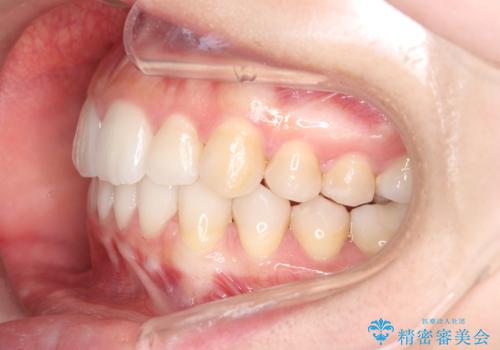

目立たない矯正で歯のデコボコと反対咬合を改善

- 前歯のデコボコ(叢生)と、前歯が上下逆の咬み合わせ(反対咬合)を主訴にご来院されました。精密検査の結果、歯列全体のスペースが不足していることが判明。患者様のご希望に合わせ、透明で目立ちにくい**インビザライン(マウスピース矯正)**による治療計画を立案しました。歯を抜かずに、歯列全体を奥(遠心)へ移動させることで、歯が並ぶスペースを確保し、叢生と反対咬合を同時に改善することを目指します。

今回の矯正治療では、透明なマウスピース型の装置インビザラインを使用しました。この装置は目立たず、取り外しが可能なため、食事や歯磨きも普段通り行えます。治療は、緻密な治療計画に基づき、段階的に作製されたマウスピースを交換していくことで、遠心移動という方法で奥歯から徐々に歯列全体を後方へ動かしました。これにより、不足していたスペースを確保し、前歯のデコボコを解消。同時に、上下の歯の前後的な関係を改善することで、反対咬合も正常な咬み合わせへと導きました。見た目も機能も改善し、自然で美しい笑顔を獲得していただけました。